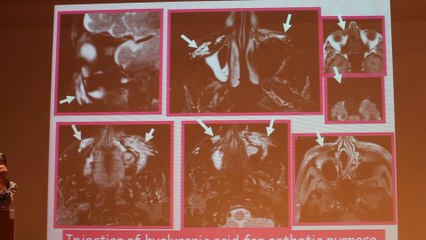

MRI of Soft Tissue Masses An Approach to Analysis - Mary G. Hochman